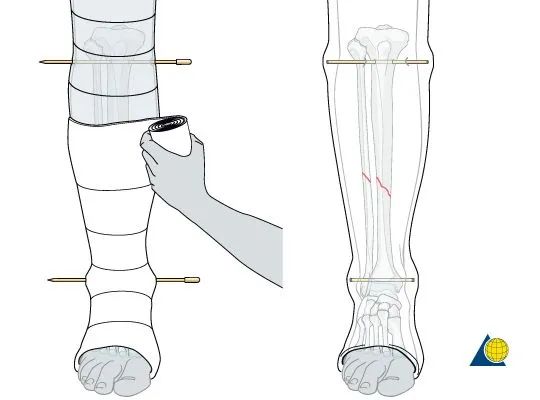

膝盖以上需要应用衬垫,

保持骨折复位的同时,

在小腿周围涂抹2-3卷,

关键部位需要重叠50%。

在脚踝处形成一个袖口,

并且进行持续的牵引,

这样的石膏有一定的牵引复位作用,

需要坚持5分钟才能使得石膏固化。

如果骨折比较容易移位,

可以将克氏针结合石膏进行固定,

这样可以更好的维持位置